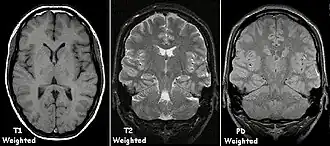

Naast de waterstofdichtheid zijn er ook andere weefseleigenschappen waarvan een plaatje te maken is, namelijk de snelheid waarmee de kernspin van aangeslagen atomen terugkeert naar de grondtoestand, de zogenoemde relaxatietijden. Zo is de tijd te meten waarin de longitudinale spincomponent voor 63% terugklapt, de zogenoemde T1. Deze is afhankelijk van de snelheid waarmee de waterstofkernen (protonen) in het weefsel de energie van hun spin afstaan in de vorm van warmte. Tevens is de tijd die het duurt voordat de transversale (dwars)component voor 63% vervalt te meten (T2). Op T1-gewogen opnamen geeft weefsel met een korte T1, zoals vetweefsel een hoog signaal waardoor het in wit op het beeld zichtbaar is. Bij een T2-opname geven weefsels met juist een lange T2, zoals vocht en vloeistoffen een sterk signaal. Een T1- of T2-gewogen afbeelding wordt vervaardigd door de fliphoek, de echotijd en repetitietijd in te stellen.

MRI-beelden worden standaard in zwart-wit afgebeeld, waarin de verschillende soorten weefsels hun eigen grijstint hebben: